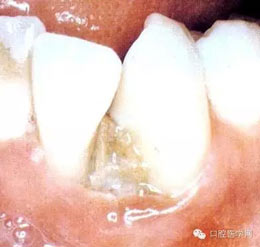

(四)壞死性齦炎:為局限的或普遍的潰瘍形成,牙間乳頭破壞,并伴有纖維蛋白性壞死。